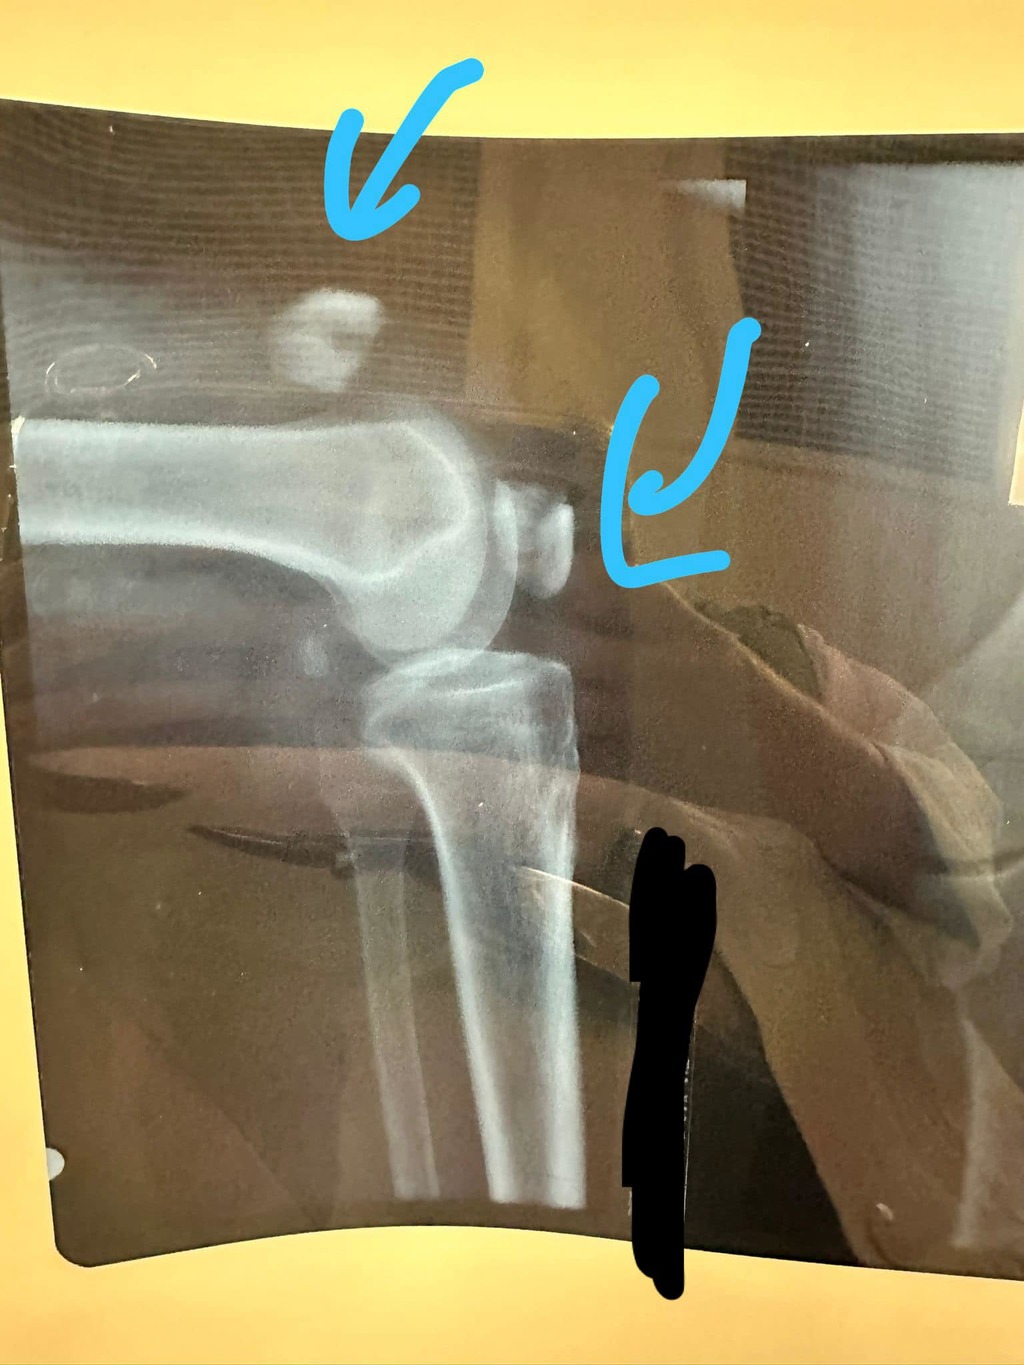

醫生:第一下跌就call白車應該唔會裂咁開

這時才有路人注意到伯伯,幫助他召救護車。在入院檢查後,醫生驚現伯伯的膝蓋已經完全碎裂,甚至傷勢嚴重需要開刀做手術,如果不接受手術,伯伯也會面臨生活上的困難,表示將會「唔做手術行唔返」。但後來,所幸伯伯的手術非常成功,醫生說,「如果第一下跌就call白車,應該唔會裂咁開,亦唔需要做手術」。